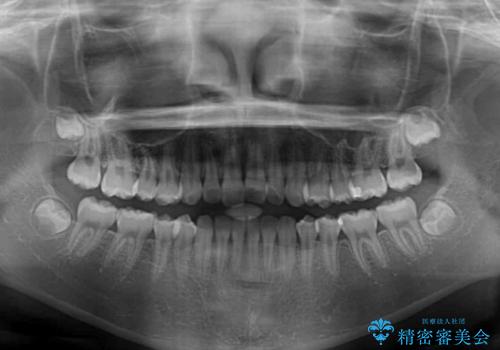

- 前歯のデコボコを気にして来院された高校生の患者様です。

捻れた前歯が前方に飛び出している点も気になっており、目立たない装置を希望されたため、インビザラインを用いて矯正治療を行うこととしました。

上下ともに少し捻れが残っていたため、治療の継続を提案しましたが、本人も親御さんも満足とのことで、治療を終えました。

捻れの改善により突出感も改善されました。